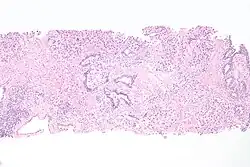

Histopathology of transitional carcinoma of the urinary bladder. Transurethral biopsy. Hematoxylin and eosin stain.

Transitional refers to the histological subtype of the cancerous cells as seen under a microscope.